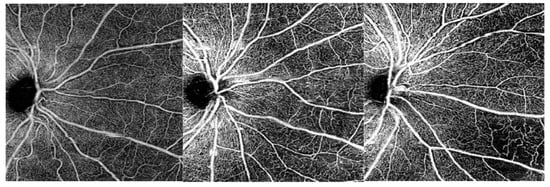

Figure 7.

OCT-A C-scans of the superficial capillary plexus (SCP). From left to right: examples of a patient without DR, a patient with mild NPDR and a patient with severe NPDR. The vessel density in the SCP progressively decreases with DR severity, especially in the most peripheral area. DR, diabetic retinopathy; NPDR, non-proliferative diabetic retinopathy.